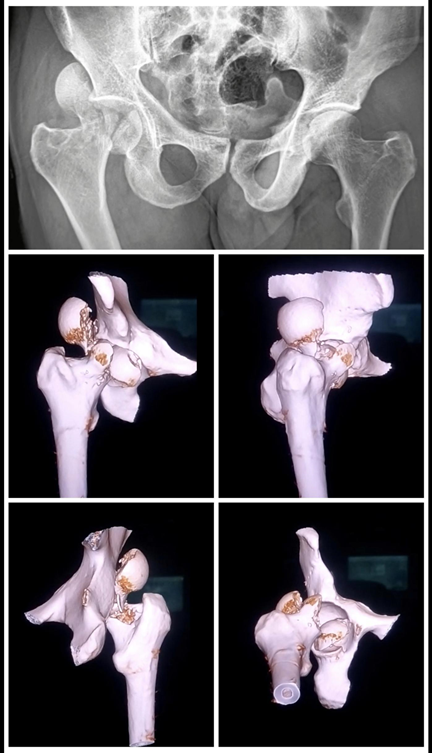

A 40-year-old male patient presented to the emergency department with acute right hip pain and inability to bear weight following a high-energy motor vehicle accident. Physical examination revealed a shortened, externally rotated right lower limb with marked tenderness over the hip region. Neurovascular examination of the limb was intact, with no distal deficits. The patient had no significant medical history, no known allergies, and no prior surgeries or fractures. Initial radiographs and CT imaging confirmed a posterior hip dislocation with a Pipkin Type III femoral head-and-neck fracture (Fig. 1). The severity of the fracture, coupled with the dislocation, placed him at a high risk for AVN and post-traumatic osteoarthritis. Given the complexity of the injury and high risk of AVN, the patient was scheduled for surgery and underwent ORIF with surgical hip dislocation and trochanteric flip osteotomy within 48 h of trauma (Fig. 2).

Figure 1: Pre-operative imaging of the affected hip showing anteroposterior radiograph and 3D computed tomography reconstruction delineating the femoral head pathology and acetabular involvement.